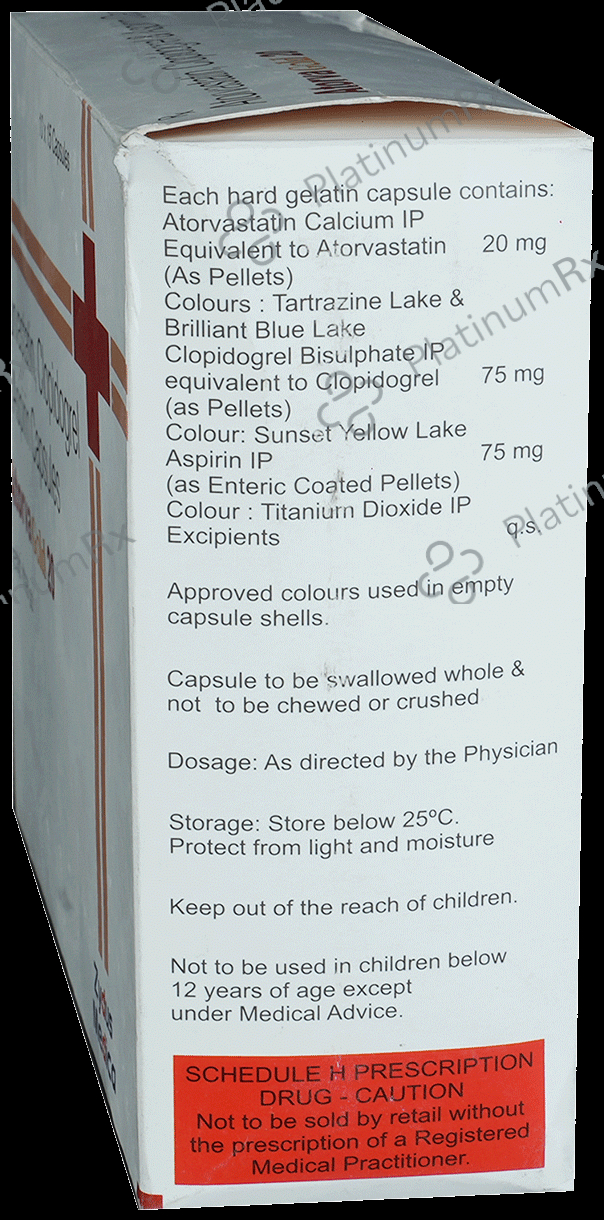

Aspirin 75mg + Atorvastatin 20mg + Clopidogrel 75mg

Salt CompositionAspirin 75mg + Atorvastatin 20mg + Clopidogrel 75mg (same for both)

Atorva Gold 20/75/75mg Capsule 15s

Atorva Gold 20/75/75mg Capsule 15s

Zydus Cadila

₹141.1